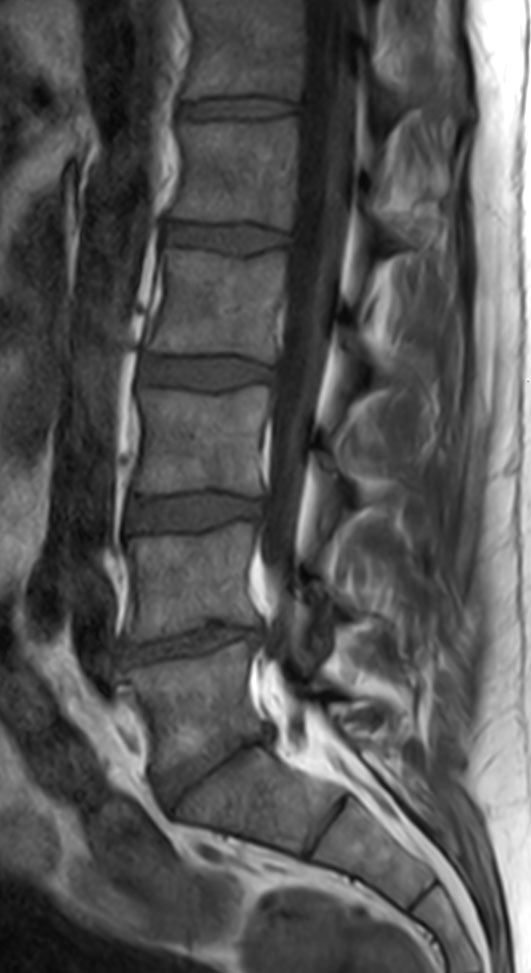

Patient with a lumbar spine bulging disc.

Sagittal T2w TSE